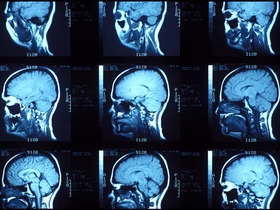

Есть две традиционных подхода к считыванию информации из мозга. При первом смотрят на общие закономерности мозговой активности, используя МРТ, ПЭТ и ЭКГ. Эти процедуры позволяют понять, что происходит с мозгом на макроуровне. Они отлично подходят для таких вещей, как изучение областей мозга, участвующих в чтении, эмоциях и движении.